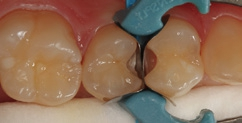

Die Zähne 24 und 25 des 51-jährigen Tierarztes wiesen diskrete, aber behandlungsbedürftige Approximalläsionen auf – gut erkennbar an der Transluzenzänderung der Randleisten in Abbildung 16. Die Abbildung 17 zeigt die exkavierten und mit FACE-Light-Kontrolle [6] als kariesfrei eingestuften Kavitäten, bereits mit Teilmatrizen und einem Spannring (Palodent V3, Dentsply Sirona) isoliert. Bei Verwendung dünner Teilmatrizen können durchaus zwei benachbarte Kavitäten gleichzeitig versorgt werden. Die noch vorhandene Schmelzlamelle zu dem Goldinlay an Zahn 25 berechtigt den Verbleib des klinisch ansonsten intakten Goldinlays. Die Abbildung 18 zeigt die Situation nach der adhäsiven Versiegelung mit einem Universaladhäsiv (Prime&Bond active, Dentsply Sirona) nach vorangegangener Schmelzätzung, die Abbildung 19 die ausgearbeiteten und polierten minimalinvasiven Slot-Füllungen – ausschließlich aus SDR flow+ in der Farbe A2. Die Polymerisation erfolgte für 40 Sekunden aus okklusaler Richtung, gefolgt von einem weiteren Polymerisationszyklus von 20 Sekunden über die bukkale Flanke. Durch die gewählte Versorgungsform ist mit Sicherheit die am wenigsten invasive und auch die für den Patienten wirtschaftlichste Versorgungsvariante gewählt worden, da ein Austausch des Goldinlays vermeidbar war.

Fall 5 Minimalinvasive Slot-Versorgung an Zähnen 13 und 14

Die Zähne 13 und 14 des 19-jährigen Patienten zeigten aktive Primärläsionen, die Anzeichen der hohen Kariesaktivität des jungen Patienten waren (Abb. 20). Beide Kavitäten wurden mit dem Komet Mikropräparationsinstrument 8830M.314012 präpariert und die approximalen Flanken mithilfe eines diamantierten, wabenförmigen Feinkornfinierstreifens WS 25F (Komet Dental) geglättet. Die Abbildung 21 zeigt die beiden präparierten Kavitäten mit bereits angelegten Palodent V3-Spannringen und Teilmatrizenfolien. Der distal gelegene Spannring wurde von seinem Ringdurchmesser nach distal orientiert, um eine bessere Zugänglichkeit zu den beiden Kavitäten zu gewährleisten. Gerade im Prämolarenbereich ist dieses Vorgehen oftmals sehr hilfreich. Die Abbildung 22 zeigt die fertige Versorgung mit SDR flow+ in der Farbe A2 nach adhäsiver Vorbehandlung mit Prime&Bond active nach Schmelzkonditionierung mit Phosphorsäuregel. Generell ist bei den Universaladhäsiven der selbstkonditionierenden Vorbehandlung des Dentins der Vorzug zu geben. Eine selektive Schmelzätzung bei so schmalen und kleinen Kavitäten ist aber nicht so einfach umzusetzen. Ein Pluspunkt bei allen Universaladhäsiven ist deren Toleranz auf eine vorangegangene Ätzung des Dentins mit Phosphorsäuregel: Diese „Etch&Rinse“-Anwendung hat keinen negativen Einfluss auf die Randintegration und die Haftung. Eine Metaanalyse zu Universaladhäsiven attestiert den milden Universaladhäsiven sehr gute Haftwerte auf Dentin im selbstkonditionierenden Modus [48]. Eine zusätzliche Phosphorsäurekonditionierung ergibt hier keine Vorteile, da die Dentin-Haftwerte sich im selbstkonditionierenden und „Etch&Rinse“- Modus nicht unterscheiden [10,56], aber auch keine Nachteile. Auch dieses Beispiel zeigt die gute Farbadaptation und Randintegration des Bulk-Flow-Komposits.